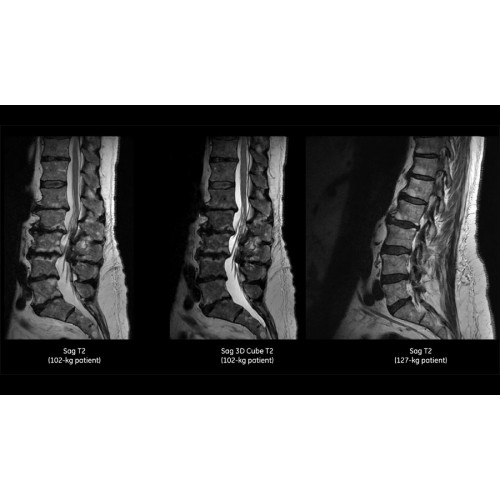

SIGNA Pioneerдает возможность использовать 3.0T там, где это было невозможно ранее. Представьте, что вы размещаете систему 3.0T в помещении, предназначенном для 1.5Т. Ее площадь размещения — одна из наименьших в своем МР-сегменте, на 25% меньше, чем у обычных систем 3.0Т.

Более низкая стоимость эксплуатации — SIGNA Pioneer потребляет на 50% меньше электроэнергии, чем обычные МРТ 3.0Т, при этом обеспечивается высокая производительность благодаря инновационной технологии сверхэффективной градиентной системы.

Система SIGNA Pioneer воплощает поразительные достижения в области визуализации. Передовая технология Total Digital Imaging (TDI) позволяет добиться большей четкости изображений и на четверть повысить соотношение сигнал/шум.